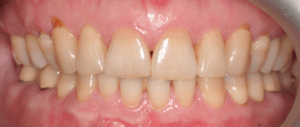

Пациентка, 43 года обратилась в клинику с жалобами на наличие промежутков между зубами, измененный наклон передних зубов верхней челюсти, появившейся за последнее время. Также пациентку беспокоил изменившийся профиль лица.

Для предварительной подготовки были привлечены пародонтолог и ортопед, поскольку отсутствие нескольких зубов, заболевание пародонта и дефекты твердых тканей зубов сопутствовали основной патологии. Проведены пародонтологические процедуры, вылечен кариес и его осложнения, изготовлены временные коронки для зубов с большим разрушением. На фото — временные коронки на боковых зубах.

Пациентка довольна профилем и красивой улыбкой.